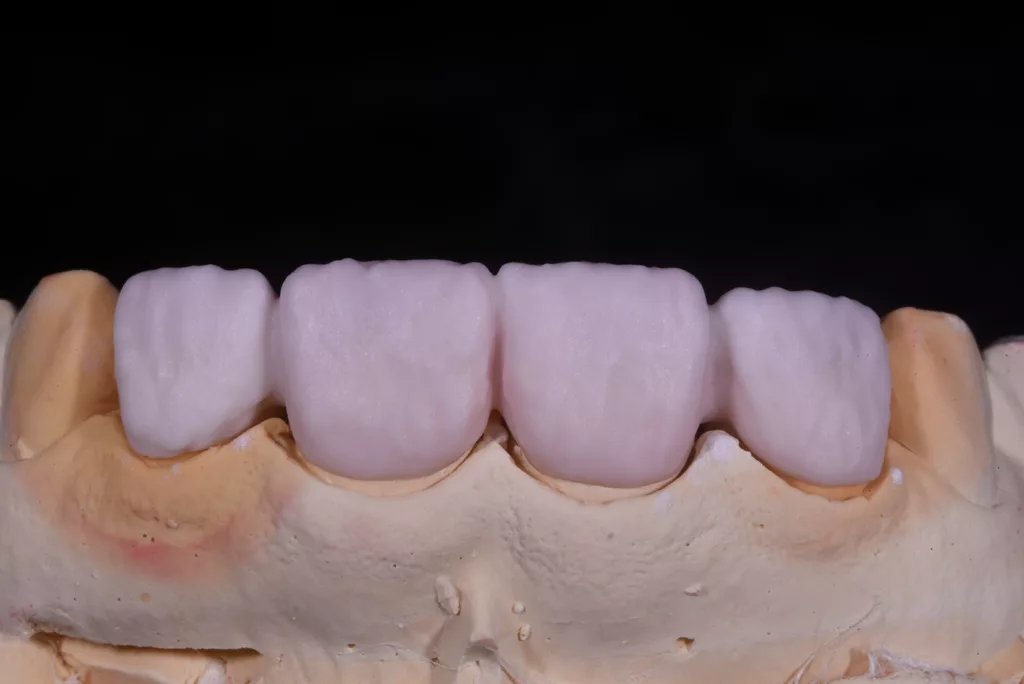

Die Kronen wurden in diesem Fall aus dem Material IPS e.max® ZirCAD Prime Esthetic von Ivoclar angefertigt. Die Transparenz des gewählten Zirkoniumdioxids ermöglichte die Fertigung dünner Kronen von 0,5 mm und gleichzeitig eine präzise Farbreproduktion ohne dicke Schichtung. Das Stumpfdesign wurde so gewählt, dass das Zirkoniumdioxid bis zur Inzisalkante reichte, um Schneidekantenfrakturen zu vermeiden. Die Schichtung erfolgte durch Auftragen von IPS e.max® Ceram Dentin-Pulver (OE1, OE2 und T1) auf das Grundgerüst (Abb. 57 bis 63).